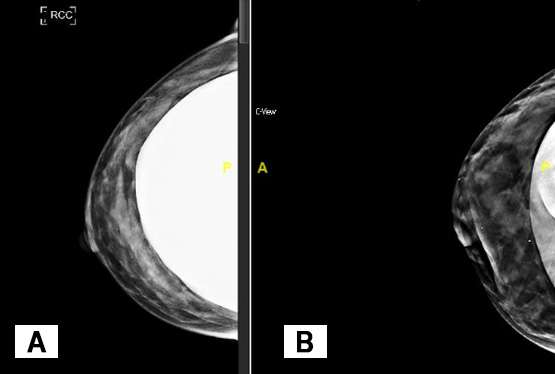

Standard craniocaudal implant included view of the right breast

Figure 3: Standard craniocaudal implant included view of the right breast (Figure 3A) and implant displaced craniocaudal view (Figure 3B), which are part of standard mammogram screenings in patients with breast implants.